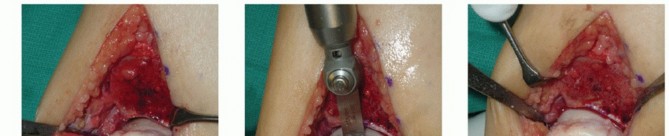

- TECH FIG 2 • A,B. Identifying the extent of the talar shoulder lesion. (continued)

Define the extent of the OLT (TECH FIG 2A,B).

Clinical inspection Review of CT scan

- TECH FIG 2 • (continued) C-E. Excision of the talar shoulder lesion using the microsagittal and oscillating saws. F. Talar shoulder lesion removed.

Excise the diseased portion of the talus (TECH FIG 2C-F).

Reciprocating and microsagittal saw (use cool saline to limit risk of heat necrosis) May need a small curette and rasp as well

Define the dimensions of the recipient site. Use a caliper and a ruler and double-check the measurements. - Harvesting Graft from Donor Talus

Carefully mark the dimensions for graft harvest on the allograft (TECH FIG 3A).

Same location on the allograft talus as the recipient site on the native talus

If you err, err to have the graft slightly too large. Be sure to account for saw blade thickness. “Measure twice and cut once.”

You have only one opportunity, so be sure the measurements and orientation of the saw blade for each cut are optimal.

The allograft can be stabilized with two large pointed reduction clamps (TECH FIG 3B).

Extract the graft from the donor talus (TECH FIG 3C).

Only once have we had a graft match perfectly on the first attempt. The graft and recipient site will almost always need to be tailored slightly to allow optimal graft fit.

It is unlikely that a perfect clinical and fluoroscopic match will be achieved. Attempt to achieve the best clinical match of the graft's articular surface with the surrounding native cartilage (TECH FIG 4A).

If the clinical match is appropriate, then the fluoroscopic match is not important.

There is a lot of variability in cartilage thickness and talar architecture in the human talus. It is difficult to get four surfaces to congruently match.

Graft fixation

Ideally, the graft will have some interference fit.

We routinely secure the graft with one or two small-diameter solid screws (1.5 or 2.0 mm in diameter). One is typically placed from dorsal to plantar and the other from medial to lateral (if the depth of the graft will allow) (TECH FIG 4B,C).

Place the screws in lag fashion.

Countersink the screw heads below the articular surface (TECH FIG 4D,E).

Using fluoroscopy, confirm that the graft and hardware are in optimal position (TECH FIG 4F-H).

The graft will not look perfect fluoroscopically, but as long as the clinical appearance is acceptable, the outcome has a good chance to be favorable.

The hardware may appear slightly proud fluoroscopically despite being countersunk. The talar dome is not a flat plane, and therefore the screw may seem to be protruding. Moreover, the articular cartilage is rather thick compared to such a low-profile screw head.

- TECH FIG 4 • A-C. Fitting and securing the graft to the native talus. A. After contouring the graft (some minor discoloration from debris while manipulating graft on back table; it is easily washed away). B. Drill hole perpendicular to graft. C. Securing graft with two countersunk screws. (continued)